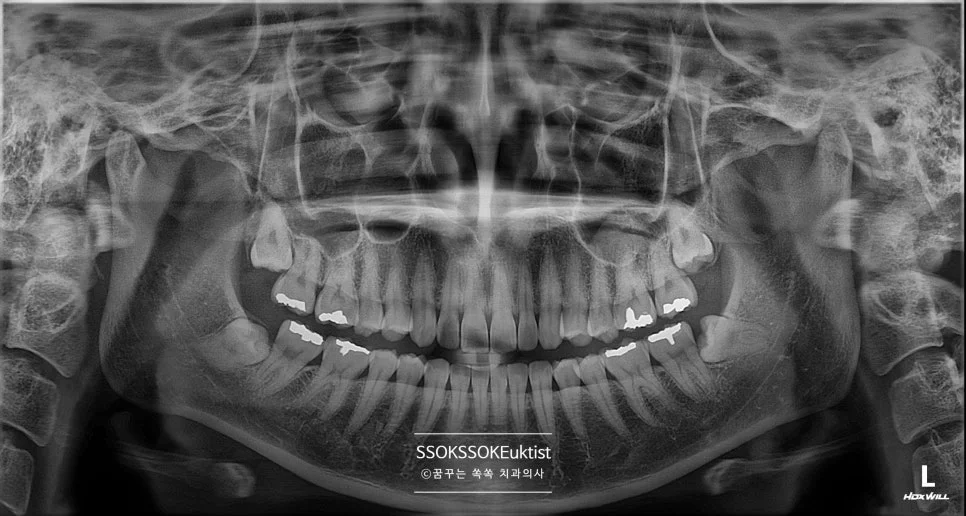

아래 사랑니 턱뼈에 걸려 잇몸 덮여 염증 발생 파노라마 X-ray

좋은 진료를 정직하게 | 선한 영향력으로 더 나은 가치를 사랑니 발치를 미루면 생기는 위험, 수면 마취로 한 번에 해결 마곡동 사랑니 꿈꾸는 쏙쏙 치과의사 박상억입니다^^ 안녕하세요^^ 오늘은 사랑니 발치에 대해 알아보려 합니다! “사랑니 발치해야 하는 건 아는데, 너무 무서워요” “한쪽만 빼도 아픈데 양쪽은 절대 못할 것 같아요” 치과를 운영하면서 제가 정말 자주 듣는 말씀인데요 파노라마 … 더 읽기